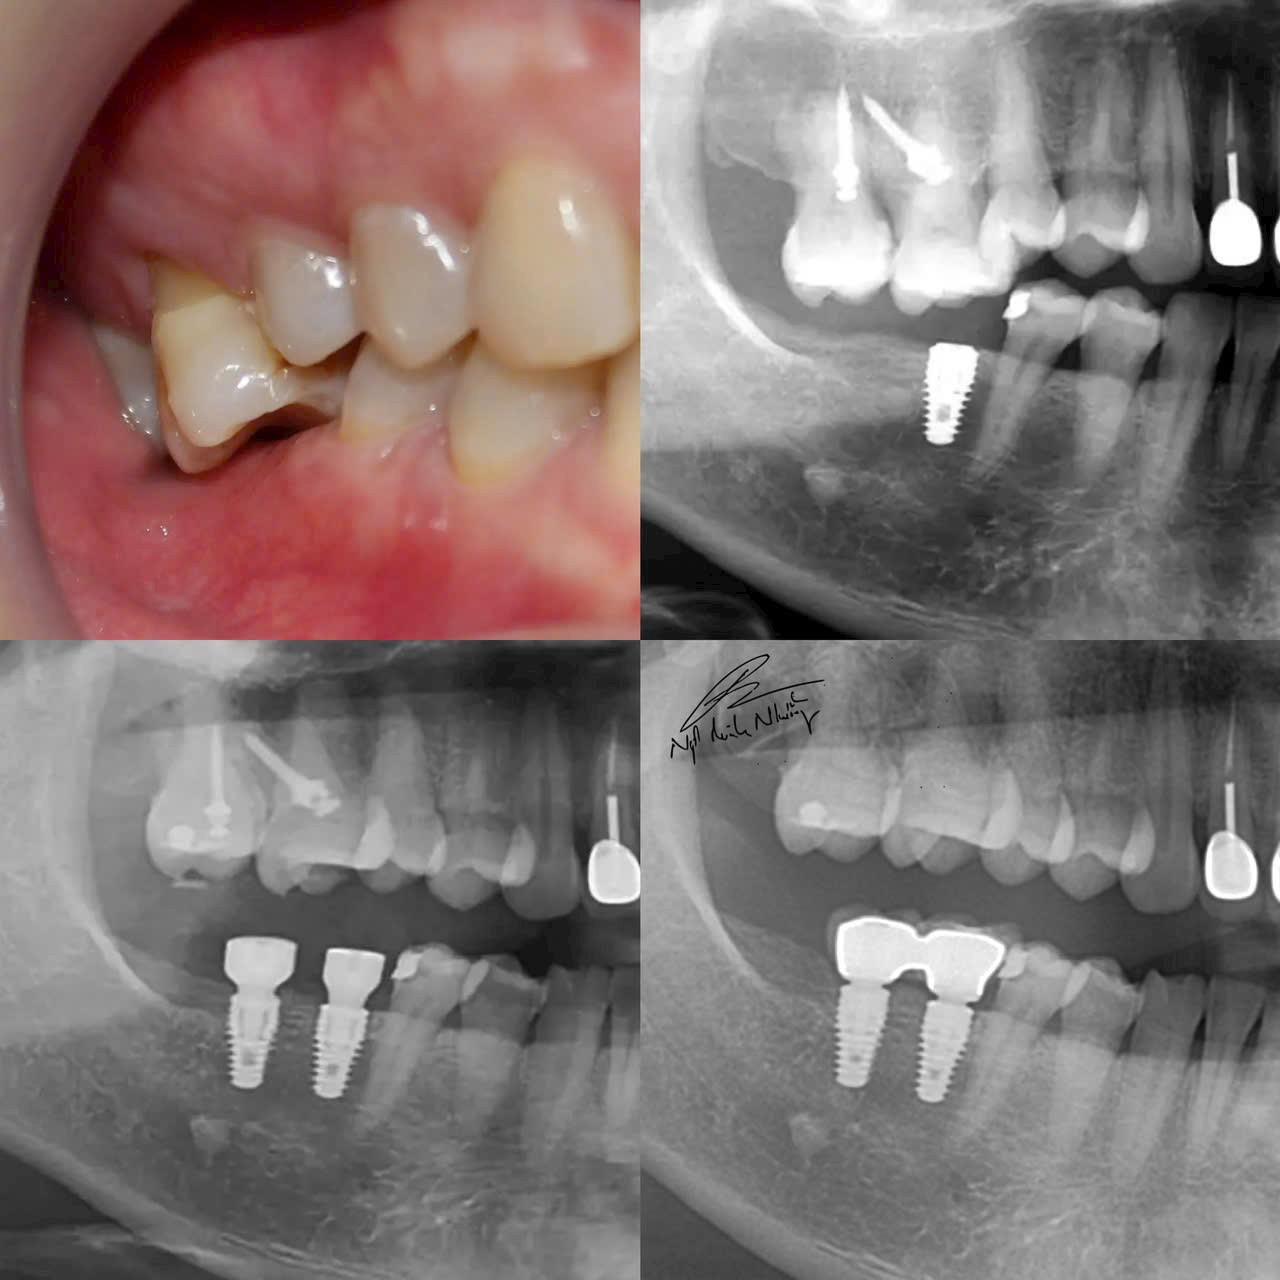

Cấy ghép răng (Implant) : Đây là phương pháp phổ biến và hiệu quả nhất để phục hồi răng đã mất. Cấy ghép răng giúp phục hồi chức năng nhai và ngăn ngừa tình trạng teo xương hàm. Cấy ghép được cấy vào xương hàm và có thể lắp răng giả lên đó.